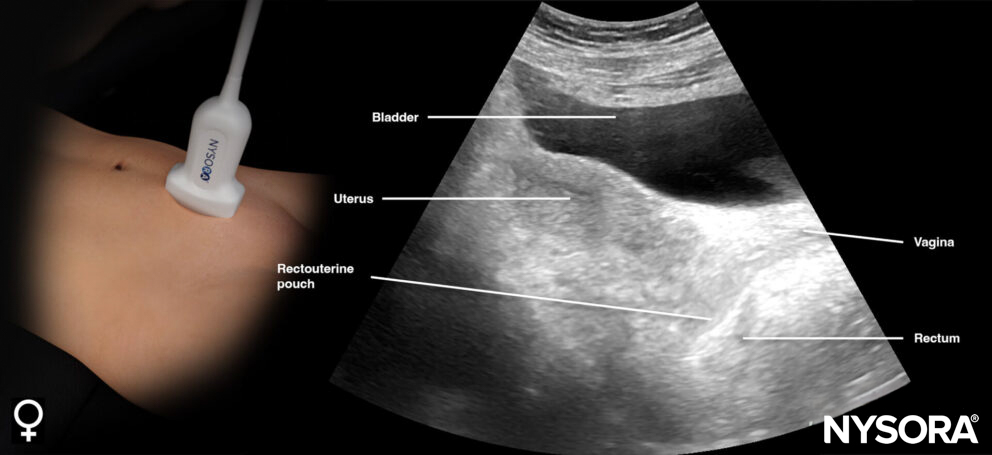

This view assesses the presence of free fluid in the pelvis.

- Position the transducer just above the pubic bone in the midline between the umbilicus and the pubic bone.

- The bladder can be used as an internal anatomical landmark to scan the area behind and lateral to the bladder for free fluid (rectovesical pouch in men and the rectouterine pouch or pouch of Douglas in women).

Normal sonoanatomy:

- Longitudinal view (orientation marker toward the head)

Sonoanatomy of interest in females:

Transducer position and ultrasound anatomy of the female pelvis.

Transducer position and reverse ultrasound anatomy of the female pelvis.